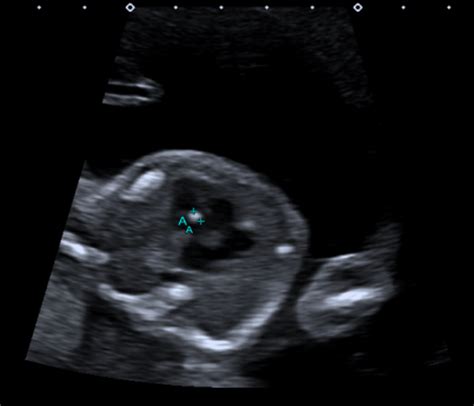

Alright, first things first: What exactly is this 20-week scan all about? In a nutshell, it’s a detailed ultrasound performed during the second trimester of pregnancy, typically between 18 and 22 weeks. This scan is super important because it provides a thorough check-up of your baby’s development. Think of it like a comprehensive health check for your little one before they make their grand entrance into the world. The sonographer, a trained professional, will use ultrasound waves to create images of your baby, allowing them to examine various aspects of their anatomy.

So, what exactly do they look for? The 20-week scan is a comprehensive assessment, covering a wide range of fetal structures and potential issues. The primary goal is to identify any structural abnormalities or birth defects. This includes checking the baby’s brain, spine, heart, kidneys, limbs, face, and other vital organs. They also assess the placenta, the amniotic fluid levels, and the umbilical cord to ensure everything is functioning correctly and supporting the baby’s growth. In India, like in many other countries, this scan is a standard part of prenatal care, giving parents and healthcare providers valuable insights into the baby’s health.

The scan allows for the early detection of many conditions. For instance, the sonographer will look for neural tube defects like spina bifida, where the spinal cord doesn’t close completely during pregnancy. They’ll also check for heart defects, which are among the most common congenital disabilities. Other conditions screened for include cleft lip or palate, limb abnormalities, and kidney problems. The scan helps to detect these issues early, allowing for timely intervention and better outcomes. The level of detail and the precision of the scan are remarkable, giving doctors a great picture of the baby’s well-being. Early detection is key , giving doctors and parents more time to prepare and make the best decisions.

It’s important to remember that the 20-week scan is not foolproof. There are limitations to what ultrasound can detect. Some conditions might not be visible at this stage, and there’s a small chance of false positives or false negatives. However, the scan provides a wealth of information, and it’s a crucial part of prenatal care. The scan itself is painless. You’ll lie down on a table, and the sonographer will apply a gel to your abdomen to help the ultrasound probe glide smoothly. They’ll move the probe around to get different views of your baby. The process typically takes about 30 to 60 minutes, depending on the baby’s position and how clear the images are. So, relax and try to enjoy the first glimpses of your baby! Bring your partner or a friend to share the experience, and don’t hesitate to ask questions. It’s all about being informed and prepared!